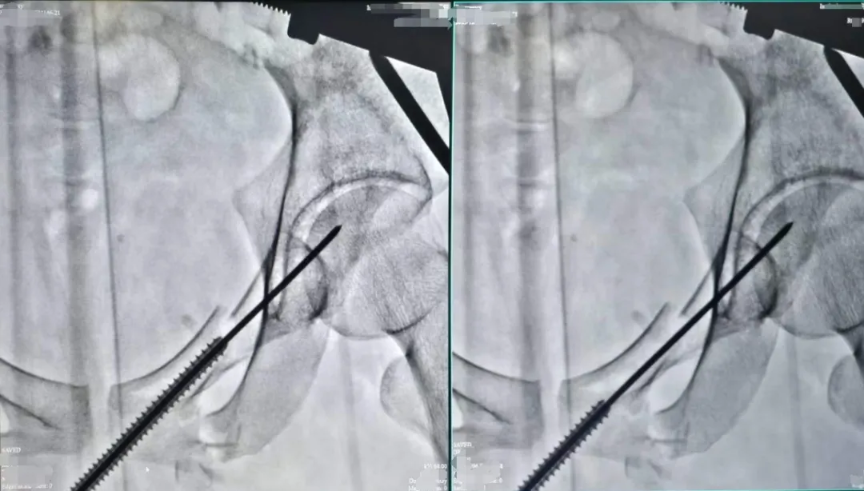

與此同時(shí),醫(yī)院創(chuàng)傷骨科團(tuán)隊(duì)積極響應(yīng)救治,根據(jù)患者的軟組織傷情和骨折程度制定出了手術(shù)方案——借助專業(yè)影像設(shè)備定位骨折部位,通過微小切口完成股骨、恥骨、橈骨等位置的骨折復(fù)位與固定。

術(shù)中透視(上)

針對(duì)小陳這樣的案例,使用的經(jīng)皮恥骨支螺釘內(nèi)固定術(shù)是一種髓內(nèi)固定技術(shù),在治療骨盆前環(huán)損傷中得到了越來越廣泛的應(yīng)用,常用于恥骨上支骨折和髖臼前柱骨折。經(jīng)過實(shí)踐分析,這是治療單側(cè)恥骨骨折的最佳治療方式,具有手術(shù)創(chuàng)傷小、術(shù)中出血量少、固定強(qiáng)度大、并發(fā)癥少及功能恢復(fù)快等優(yōu)點(diǎn)。